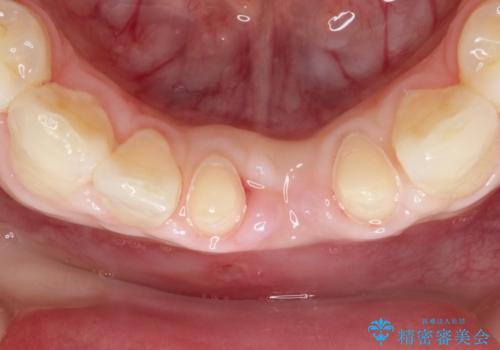

- 晩期残存した下顎乳中切歯の変色を主訴に来院されました。

後続永久歯は先天性欠如しており、下顎前歯のブリッジにて補綴治療を行なっております。